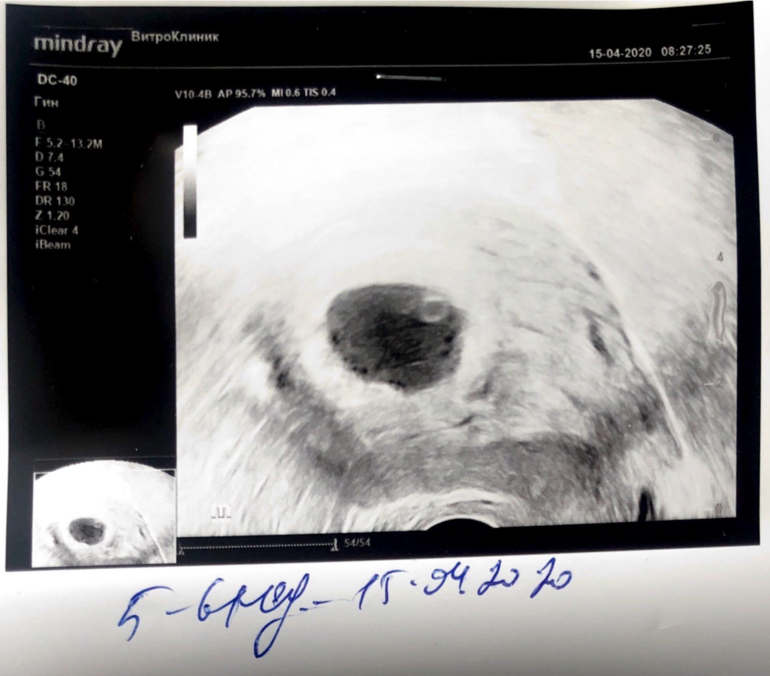

УЗИ, КТГ, доплер15.04.2020, сегодня 29 день после овуляции, т.е. 4 недели эмбрионального срока

КТР 0,36; СБ+